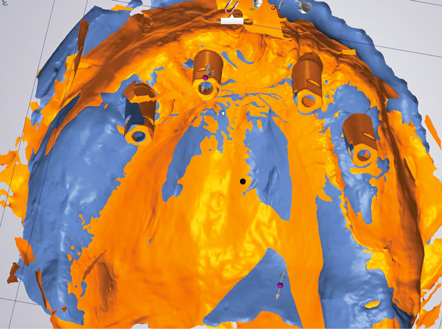

Fig 12. Virtual planning of a posterior implant (Fig 12) resulted in inadequate restorative running room for the crown emergence profile in the cross-sectional CBCT image. Revision (Fig 13) resulted in deeper positioning of the implant for restorative running room but necessitated transcrestal sinus elevation, possibly with the addition of bone via the osteotomy to tent the membrane.

Figure 12

Fig 13. Virtual planning of a posterior implant (Fig 12) resulted in inadequate restorative running room for the crown emergence profile in the cross-sectional CBCT image. Revision (Fig 13) resulted in deeper positioning of the implant for restorative running room but necessitated transcrestal sinus elevation, possibly with the addition of bone via the osteotomy to tent the membrane.

Figure 13